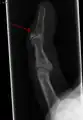

Le diagnostic est généralement basé sur les symptômes et confirmé par des radiographies[1]. La lésion peut être accompagnée d'un œdème et d'une ecchymose[3].

Radiographie montrant une fracture à l'insertion du tendon extenseur